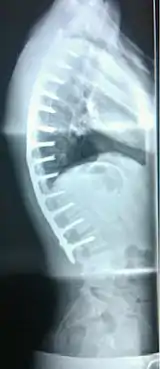

Scheuermann's disease

Scheuermann's disease is a self-limiting skeletal disorder of childhood. Scheuermann's disease describes a condition where the vertebrae grow unevenly with respect to the sagittal plane; that is, the posterior angle is often greater than the anterior. This uneven growth results in the signature "wedging" shape of the vertebrae, causing kyphosis. It is named after Danish surgeon Holger Scheuermann.[3][4][5]

| Scheuermann's disease on lateral Xray of the T spine | |